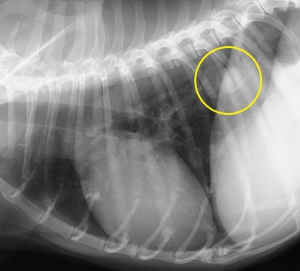

次にイメージングプレートのCRレントゲンとFPDによるDRレントゲンの画像比較をしてみたいと思います。下の写真はそれぞれ同じ猫の正常な胸部レントゲン写真です。違いがお分かりになるでしょうか?

上がCRで下写真が次世代のDRによるものです。

DRレントゲンの画像の方がくっきり明瞭に見える一方、CRではやや曖昧な印象を受けると思います。

下2枚の写真は同じ犬の胸部レントゲン写真です。どちらも黄色の丸の中に白い円形の何かが見えると思います。

実はこの写真は肺転移した腫瘍のパターンなのですが、上のCRより下のDRの画像の方がよりはっきりと異常を確認できます。どちらも同じデジタルレントゲンなのですが、異常を際立たせるという意味でもDRに優位性があります。